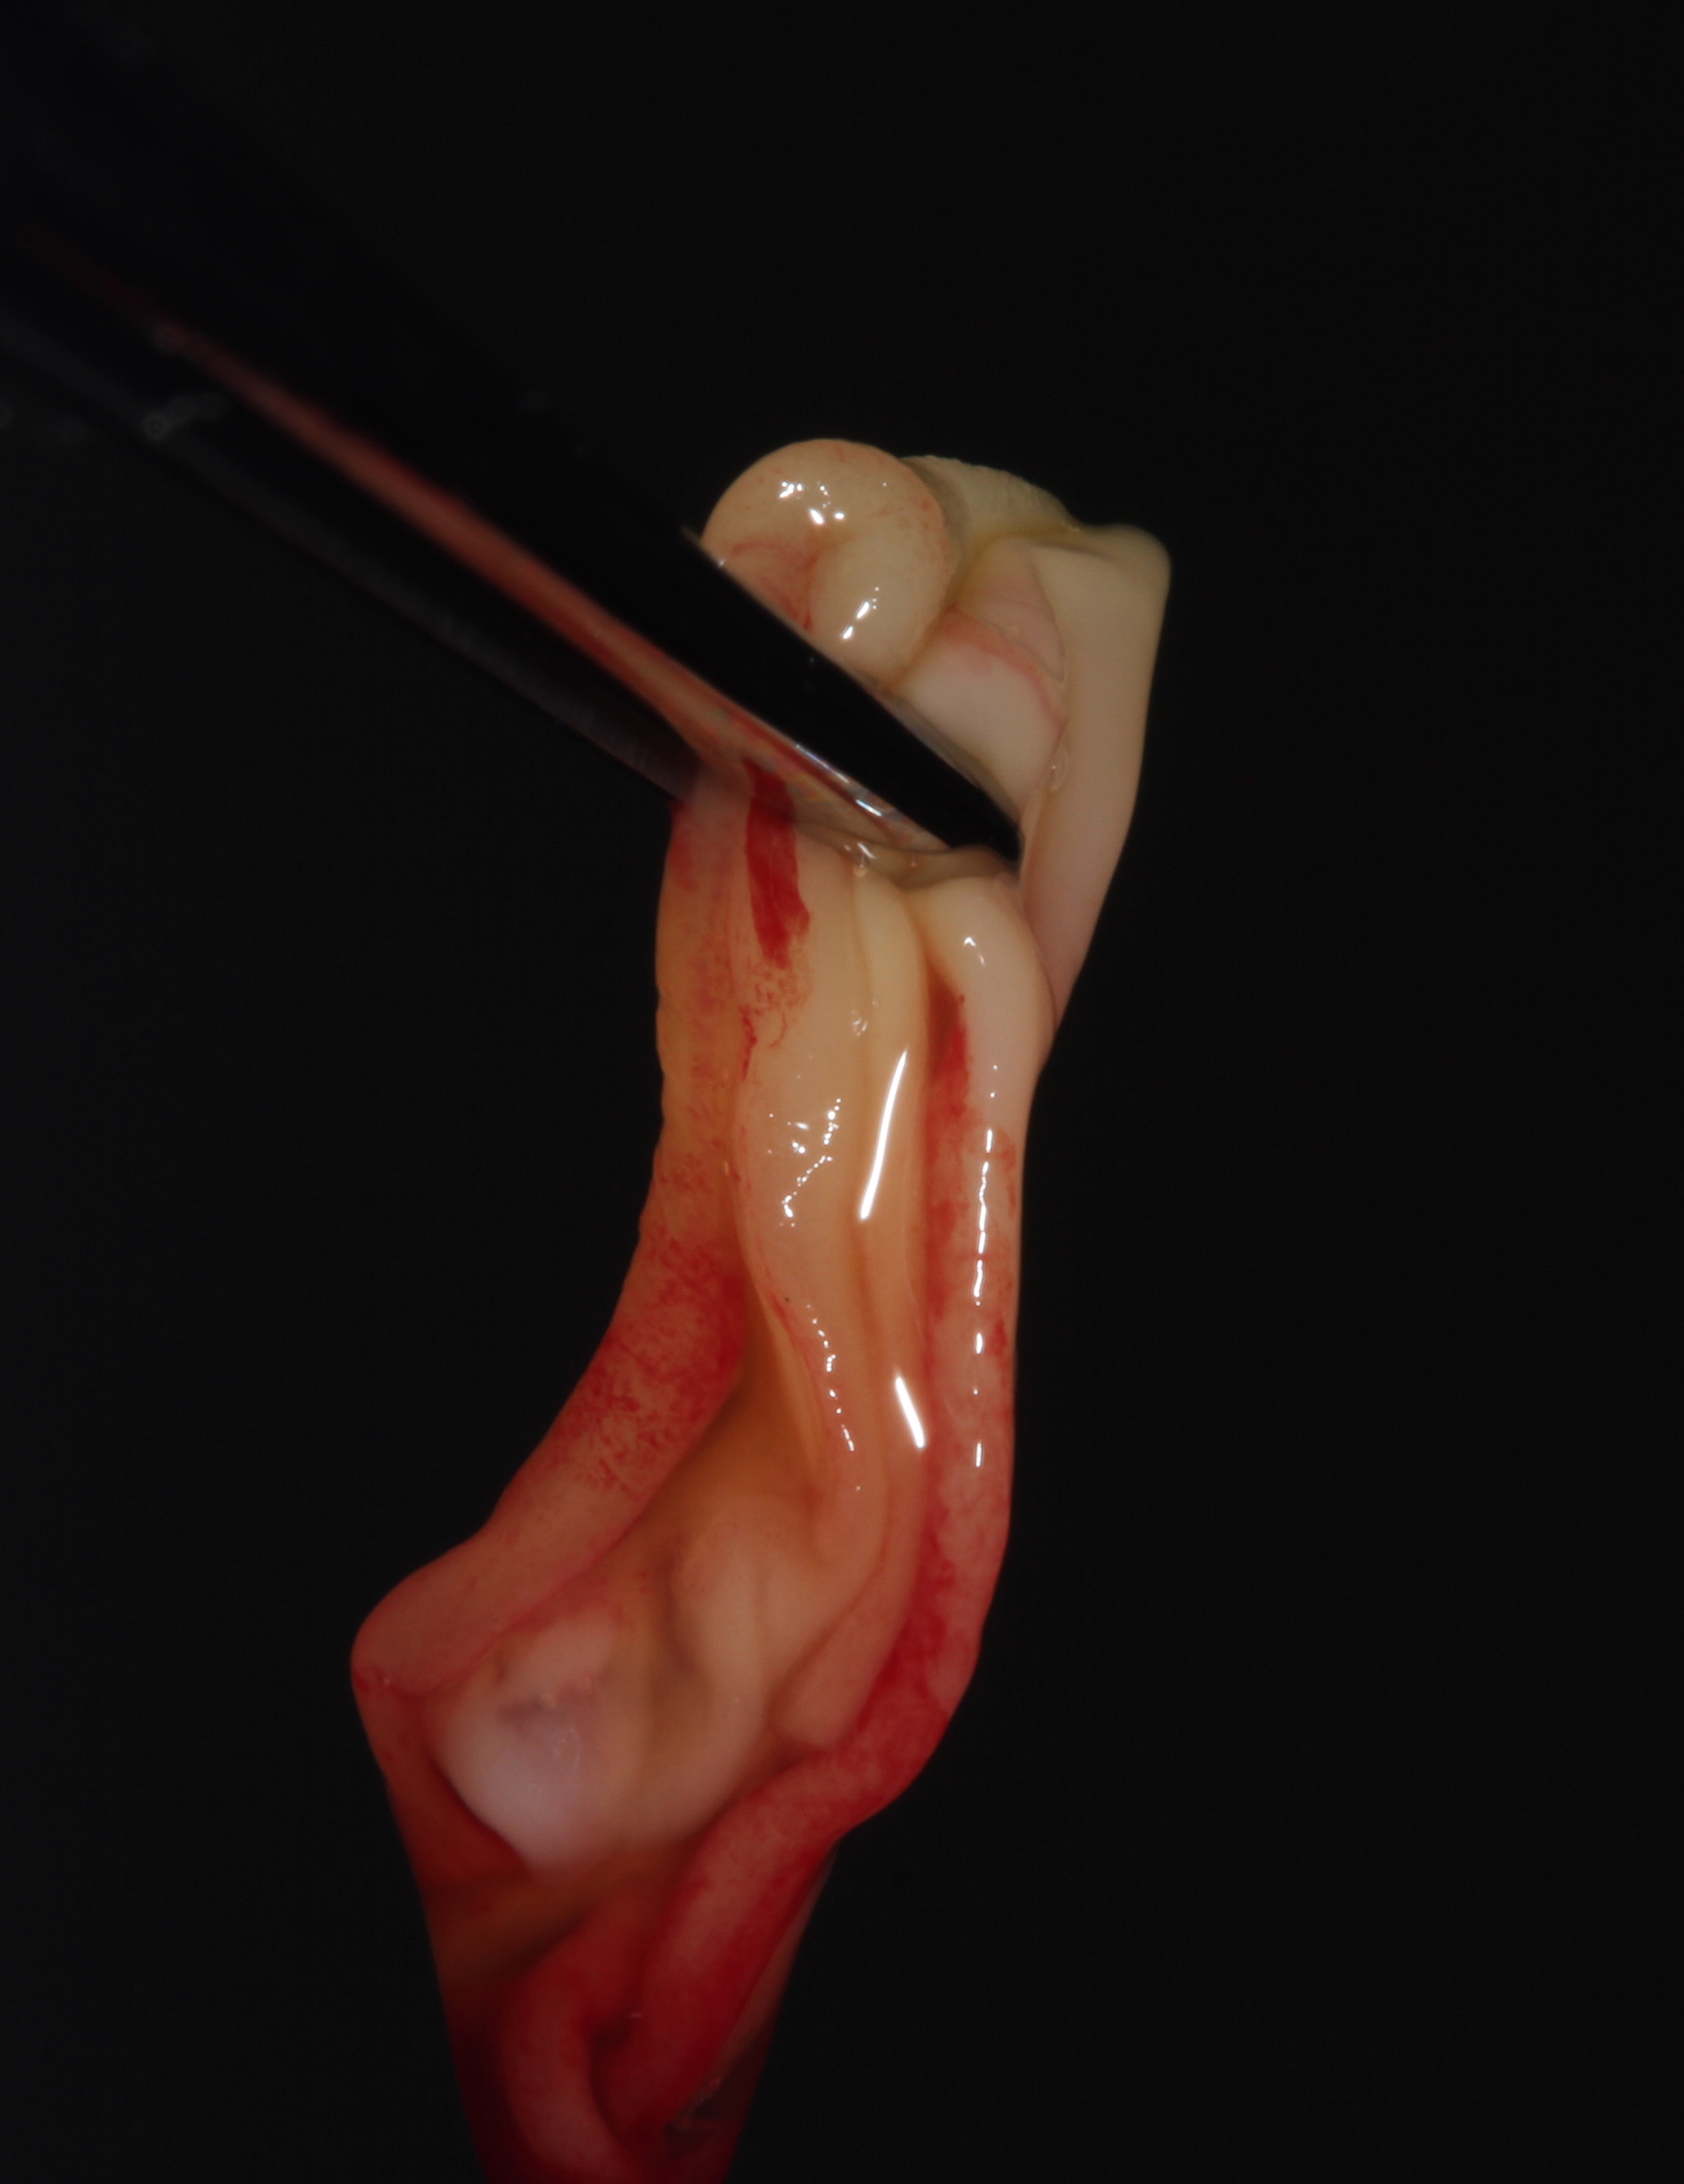

Fig 4. APRF membrane handling. The membranes formed are ready to be placed under the flap. Three to 4 membranes per pair of teeth will offer adequate volume and cellular release.

Figure 4

In a quantitative histomorphometric analysis of cell penetration, Gahnaati et al7 evaluated the composition of APRF membranes. Sixty-eight percent of the APRF membranes were colonized by the platelet-derived growth factors harvested by the samples. These findings, correlated with the authors’ clinical experience, led to a conclusion that 3 to 4 membranes are needed per pair of teeth to clinically observe a fibropromotion (Figure 2 through Figure 4).